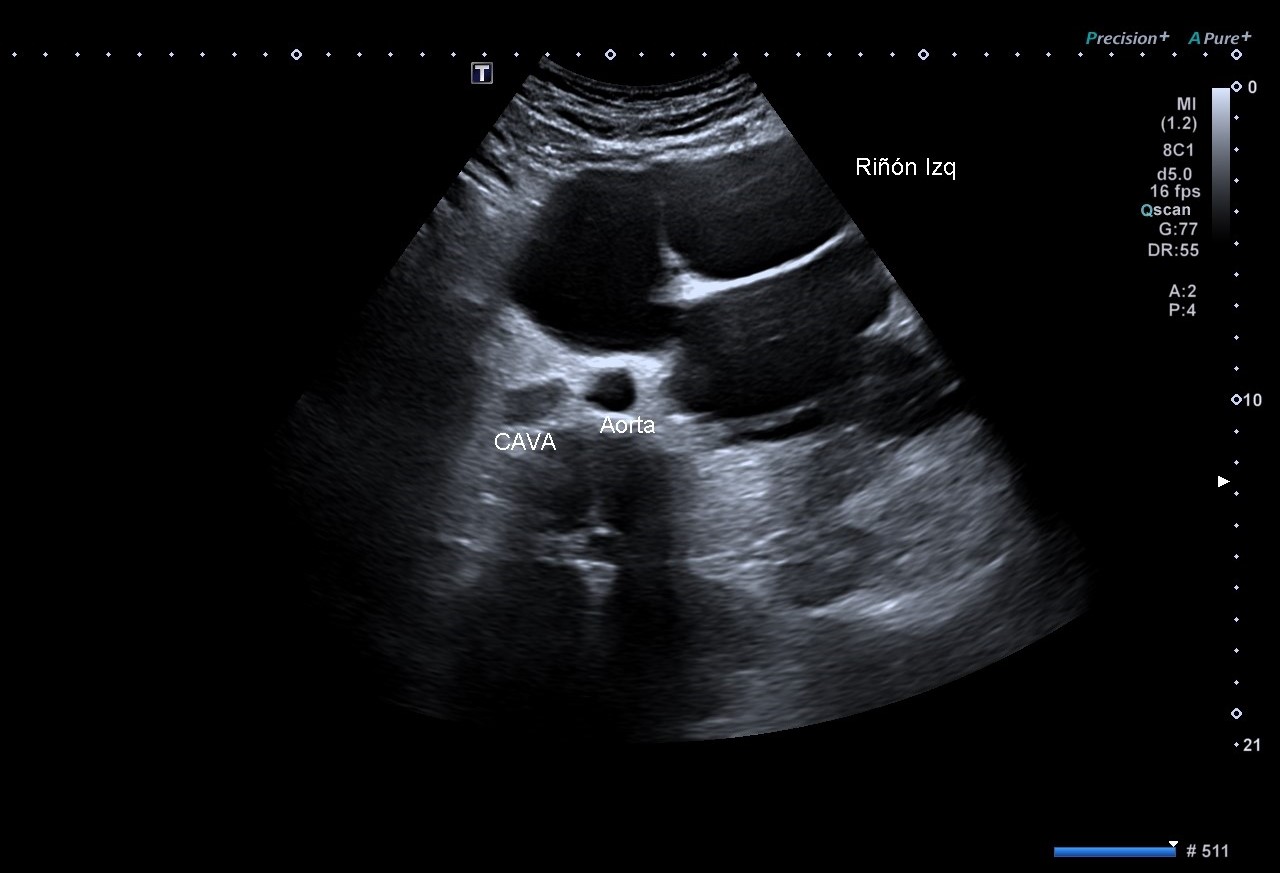

En la EcoAP se objetiva vejiga urinaria de paredes lisas, con volumen pre-miccional de 731.1cc, jet urinario derecho presente pero izquierdo no visualizado, y volumen post-miccional de 15.2cc.

Se evidencia riñón izquierdo con hidronefrosis grado 4+, completamente desestructurado que impiden reconocer arquitectura renal normal, con múltiples imágenes anecoicas, aumentado de tamaño llegando a sobrepasar línea media. Destaca una imagen hiperecogénica con múltiples sombras acústicas posteriores, compatible con litiasis coraliforme, en concordancia con la radiografía.

El riñón derecho presenta morfología y localización normales (13,2 cm).